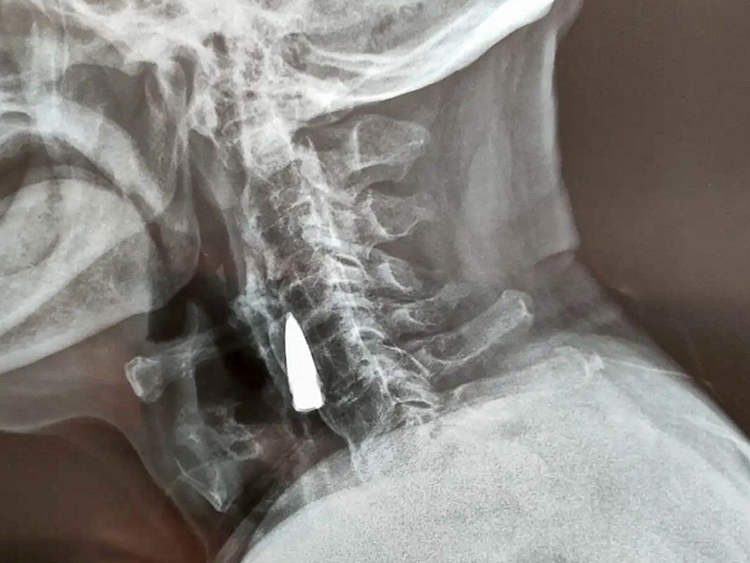

Viên đạn nằm trong cổ 77 năm mà bệnh nhân không hay biết